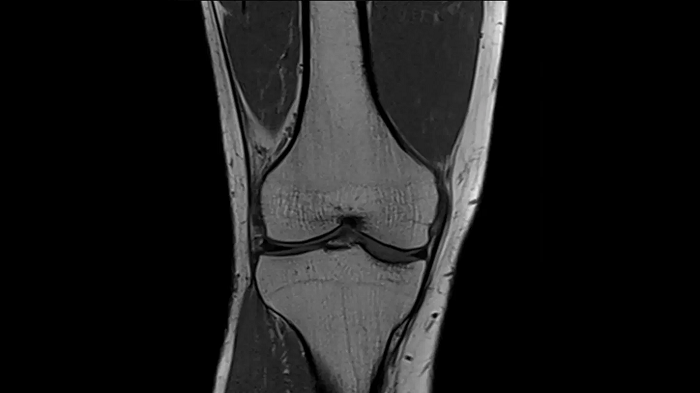

Knee

PD TSE Fat Sat with Deep Resolve and Simultaneous Multi-Slice

For clear imaging of the knee, outstanding fat suppression and performance are possible. Integrating the influence of Deep Resolve with the established Simultaneous Multi-Slice technique.

SMS 2 | Deep Resolve Gain & Sharp

0.4 x 0.4 x 3.0 mm2

TA 2:56 minutes

MAC-ID: 7aaaa0198. Image Credit: Siemens Healthineers

PD TSE Fat Sat with Deep Resolve and Simultaneous Multi-Slice

For clear imaging of the knee, brilliant fat suppression and performance are possible. Integrating the influence of Deep Resolve with the proven Simultaneous Multi-Slice technique.

SMS 2 | Deep Resolve Gain & Sharp

0.3 x 0.3 x 3.0 mm2

TA 2:16 minutes

MAC-ID: 7aaaa0198. Image Credit: Siemens Healthineers

T1 SE

Outstanding T1 imaging of the knee using MAGNETOM Free.Star.

0.3 x 0.3 x 3.0 mm2

TA 2:54 minutes

MAC-ID: 7aaaa0198. Image Credit: Siemens Healthineers

3D MSK Imaging with Compressed Sensing

Knee imaging with T2w SPACE can be expedited using Compressed Sensing to reduce acquisition times, offering high-resolution images for uncompromised knee assessments.

Compressed Sensing 6

0.3 x 0.3 x 0.6 mm2

TA 4:15 minutes

MAC-ID: 7aaaa0175. Image Credit: Siemens Healthineers